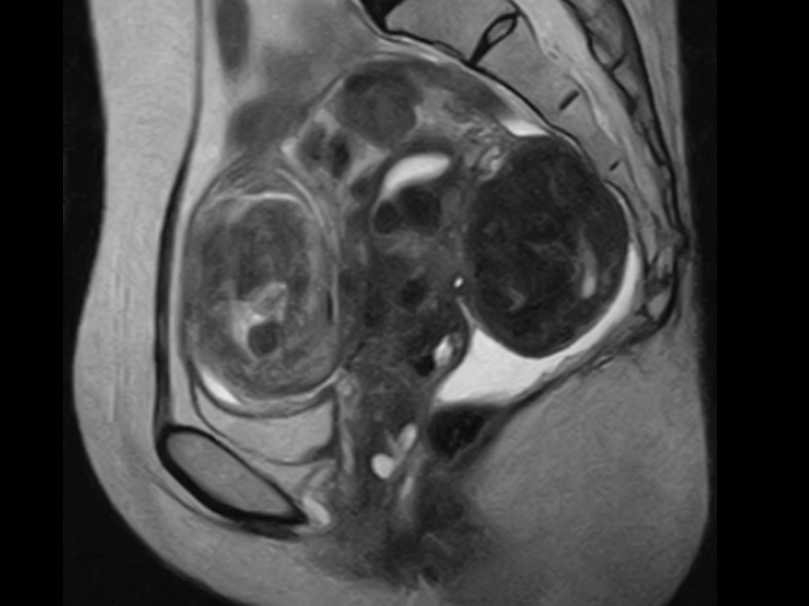

MRIドックのご案内

当クリニックでは脳神経外科領域の診療の他にMRIを用いた様々な検診メニューをご用意いたしました。『病状はなく病院へ行くほどではないけれど何か気になる』『ご自身の体の状態を正確に知りたい』などの場合にお役に立てる事と存じます。

病気の早期発見のために、最新のMRIを用いた本格的な検診。

大病院などで用いられている最新のMRIを使用し、精度の高い結果を得、かつ痛みや不快感を極力排除することを可能にしました。

検査画像は、豊富な経験を持つ専門性の高い読影医が担当し、読みやすく質の高いレポートとしてご提供します。また、ご要望に応じて、医師の説明を受けながら、自分の目で検査の画像を確認し、現在の健康の状態を理解して頂くことも出来ます。